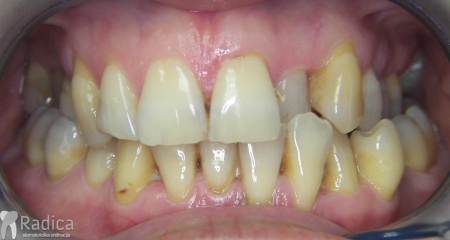

Danas je sve veći broj odraslih pacijenata u terapiji. Pod „odraslim pacijentom“ u ortodonciji se smatraju svi pacijenti koji su završili rast i razvoj – prosječno nakon 18 – 20 godine života. Kako se sa starenjem smanjuje broj stanica i prokrvljenost koštanog tkiva terapija obično traje duže i retencija je doživotna. Također, kako veći broj pacijenata dolazi s već izgubljenim zubima, abradiranim (potrošenim) zubima i poremećenom okluzijom, očekivanja od ortodontske terapije trebaju biti realna, a ne idealna.

Dakle, poslagat ćemo zube koje imamo, osigurati okluziju, stvoriti prostor za nadoknadu nekih zuba i samim tim spriječiti daljnje propadanje zuba i zagriza ali rezultat će biti „realan“ i daleko od onog idealnog rezultata kojeg možemo postići kod mladih osoba koje imaju sve zube.

Međutim, jedan od uzroka parodontitisa je loš položaj zuba i posljedično loš zagriz. Kod lošeg zagriza opterećenje zuba prilikom žvakanja je patološko. Zub nije opterećen po njegovoj dužinskoj osi – što ga štiti od oštećenja – nego je opterećen drugačije. Uslijed toga dolazi do naginjanja zuba, gubitka kosti, povlačenja zubnog mesa i ogoljenja korijena zuba.

U galeriji slika su prikazani klinički slučajevi ovakvih odraslih pacijenta bilo da se radi samo o ortodontskoj terapiji ili predprotetskoj ortodonciji.